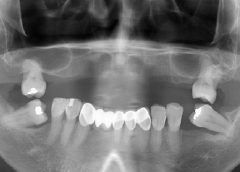

• Tình trạng mất răng:Mất răng toàn hàm lâu năm và tiêu xương hàm nặng.

Mất răng toàn hàm và phải sử dụng hàm tháo lắp lâu năm không chỉ khiến cô Bạch Thúy ăn nhai khó khăn, mà còn gặp biến chứng tiêu xương nghiêm trọng. Khiến khuôn mặt của cô bị hóp một bên má và trông già hơn tuổi thật rất nhiều.